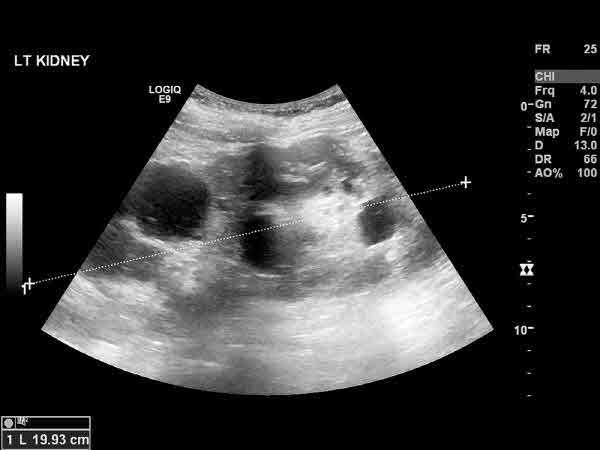

6일 질병관리청 국가건강정보포털에 따르면 다낭성 난소 증후군은 호르몬 불균형 등으로 인해 생기는 내분비질환으로, 가임기 여성의 약 6∼15%에서 관찰된다. 일반적으로 생리 불순, 남성호르몬 증가, 초음파 검사 결과상 특이사항(난소에 2∼9㎜의 난포가 12개 이상 보이거나 난소 부피가 10㎤ 이상) 중 두 가지 이상의 증상이 나타나는 경우를 말한다.